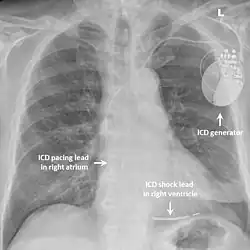

Implantable cardioverter-defibrillator

While medication and sympathectomy aim to prevent abnormal heart rhythms from occurring in the first place, an implantable defibrillator (ICD) may be used to treat arrhythmias that medication has failed to prevent and restore a normal heart rhythm.[2] These devices, usually implanted under the skin at the front of the chest below the shoulder, can continuously monitor the heart for abnormal heart rhythms. If a life-threatening arrhythmia is detected, the device can deliver a small electric shock to terminate the abnormal rhythm and restart the heart.[1]

Implantable defibrillators are often recommended for those with CPVT who have experienced blackouts, ventricular arrhythmias or cardiac arrest despite taking appropriate medication.[2] These devices are life-saving, as it has been shown that their use confers a significant survival benefit in patients with CPVT.[25] It has been suggested that the resulting surge of adrenaline caused by the pain of an electric shock from the device could theoretically bring on a cycle of recurrent arrhythmias and shocks known as an electrical storm,[4] and therefore it is strongly recommended that those with an ICD implanted for CPVT take a beta blocker to dampen the effects of adrenaline.[4]